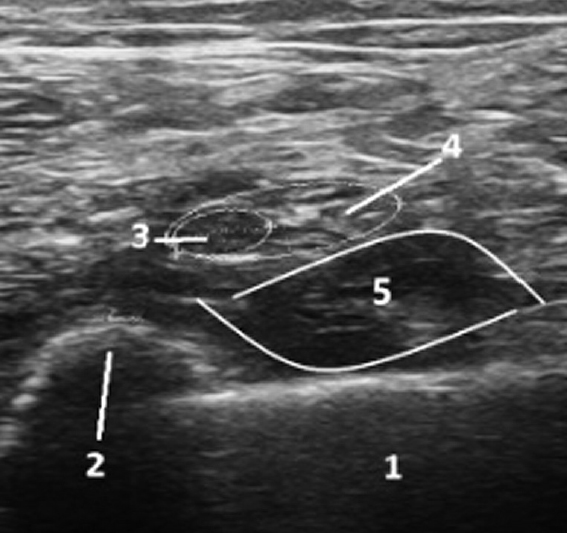

В ряде наблюдательных исследований, проходивших в разных странах мира, было показано, что эффективность монотерапии невропатической боли в реальной практике составляет в лучшем случае 20–30 % [14]. В соответствии с клиническими рекомендациями назначение комбинированной терапии при НБС следует рассматривать в случаях, когда монотерапия в эффективных дозах на протяжении 3 мес лечения привела к снижению интенсивности боли не больше чем на 30 %, или на ее фоне боль сохраняется на уровне 5 баллов по 11-балльной ЦРШ, а болевой синдром при этом приводит к значительному ухудшению качества жизни [15]. Невролог, оказывающий помощь раненым с НБС травматического генеза, в т. ч. с ФБС, не имеет такого запаса времени, поэтому, исходя из нашего опыта, к назначению комбинированной терапии следует прибегать сразу же после установления неэффективности монотерапии максимально разрешенными дозами препаратов либо в случае появления нежелательных явлений в процессе титрации их доз. Наиболее зарекомендовавшей себя комбинацией при лечении НБС сильной интенсивности является применение габапентина (1800–2700 мг/сут) и амитриптилина (75–100 мг/сут). При неэффективности данной комбинации возможно назначение адъювантной терапии в виде неклассических анальгетиков (нефопам); препаратов, обладающих нейромодулирующим действием на антиноцицептивные системы (агонисты D2-дофаминовых рецепторов, блокаторы глутаматных NMDA-рецепторов); проведение лечебно-диагностических блокад (например, блокады звездчатого ганглия при травматических плечевых плексопатиях под УЗИ-навигацией, рис. 4, 5), продленной региональной анестезии (на период титрации доз лекарственных препаратов).

Рис. 4. Ультразвуковая навигация при выполнении блокады левого звездчатого ганглия. 1 — инъекционная игла; 2 — передняя лестничная мышца; 3 — общая сонная артерия; 4 — длинная мышца шеи; 5 — поперечный отросток 6-го шейного позвонка; 6 — звездчатый ганглий